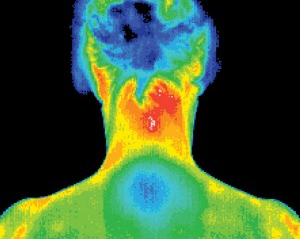

Thermography is digital infrared imaging (DII). Using a highly sensitive, thermal imaging camera, digital infrared imaging accurately measures heat from the surfaces of the breasts, detecting temperature differences. It is non-invasive, radiation-free and there is no compression. DII can detect benign tumors, simple cysts, fibrocysts, infections and other conditions.

Simply put, we all have our own unique, set patterns in our breasts, like a “thermal fingerprint”. These patterns should never change and will remain constant throughout our lives. Before a tumor begins to grow, it has to establish its own network of blood vessels, a new blood supply to feed it. This new network of vascularity changes your set patterns. A thermogram can detect these changes within two years of its onset.

The ideal early warning system would detect both the pre-cancerous changes occurring in the breast and the first cancer cell formations. Digital Infrared Imaging has the ability to detect the chemical and blood vessel changes in pre-cancerous as well as cancerous breast tissue. DII can be the first indicator that a cancer may be forming or present; and in many cases from 8-10 years before it can be detected by any other method.